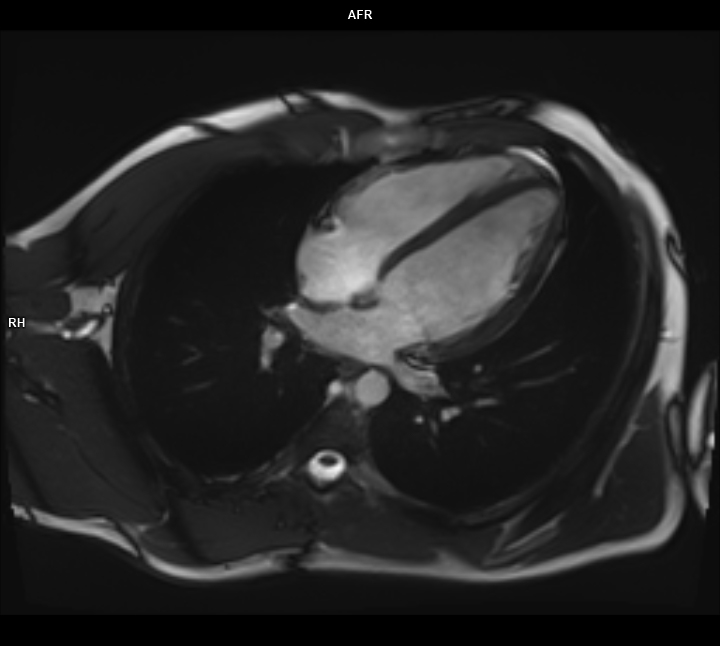

• Kardiyak MR

• 3 TESLA MR ÇEKİM GÖRÜNTÜLERİ

3 Tesla MR Çekim Görüntüleri

• 3 Tesla MR Çekim Görüntüleri